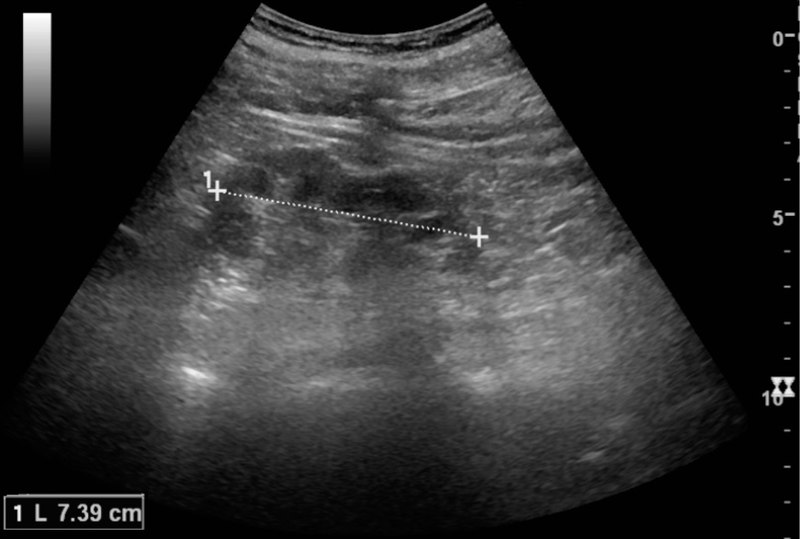

Nephrolithiasis

Nephrolithiasis is the formation of a stone from a urine solute.

Nephrolithiasis presents as:

- Colicky pain

- Hematuria

- Tenderness on one flank